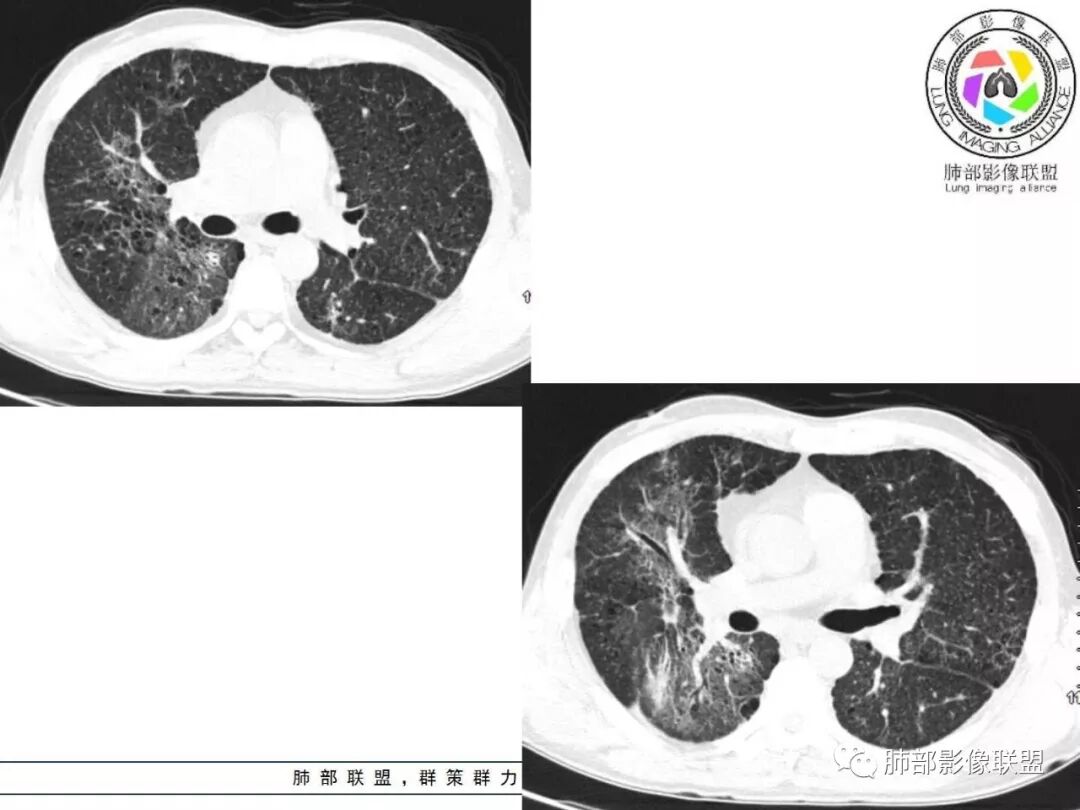

胸部CT:两肺弥漫病灶,磨玻璃影,少许实变,部分累及胸膜,磨玻璃区可见囊?少许胸腔积液,两肺可见结节,支气管血管束增粗,小叶间隔增厚,支气管走形有扭曲扩张,可见纤维化。气肿、大泡。考虑:感染性病变,PCP?查下HIV,CD4,G等。鉴别结核、结缔组织病肺浸润。

患者中年男性,发热1月,体温38℃-39℃,峰值40℃,无畏寒、寒战,伴黄痰,CRP升高明显,降钙素原稍升高,血沉、血糖正常。胸部CT:两肺弥漫病变,磨玻璃影+点片渗出,部分累及胸膜,磨玻璃区边界清楚,少许胸腔积液,两肺支气管血管束增粗,小叶间隔增厚,部分支气管走形有扭曲扩张,可见肺气肿、右肺尖肺大泡及部分纤维化改变。综合考虑:感染性病变。结核或PCP可能性大,鉴别风湿免疫、结缔组织疾病肺浸润和腺癌等恶性病变。

双肺弥漫性病变,多发磨玻璃密度及小叶间隔增厚,大部分沿支气管血管束分布,伴支气管轻度扩张,以午后及晚上发热为主,考虑感染性病变,间质性结核可能大,另双肺多发肺气囊,LIP待排

病灶呈片状磨玻璃密度影,呈典型的烟花征。磨玻璃影密度偏高,有网结节样改变,与正常肺实质分界清楚,且常见相对高密度的勾画。

烟花征分为3肿类型:晕征、反晕征及均匀分布。

2. 肺气肿背景(小叶中心性肺气肿);双肺多发病灶整体沿血管支气管束及胸膜下分布,以上叶及下叶背段分布为主,有实变及GGO,边界清楚,有树芽,小叶间隔及中央间质增厚,叶间裂见到多发结节,部分支气管不规则牵拉扩张,提示病灶纤维化明显,结合临床病史,考虑病灶为间质性感染,肺门及纵隔内有钙化淋巴结,小叶间隔结节,考虑淋巴道增值性疾病可能,综合常规要怀疑间质性肺结核。